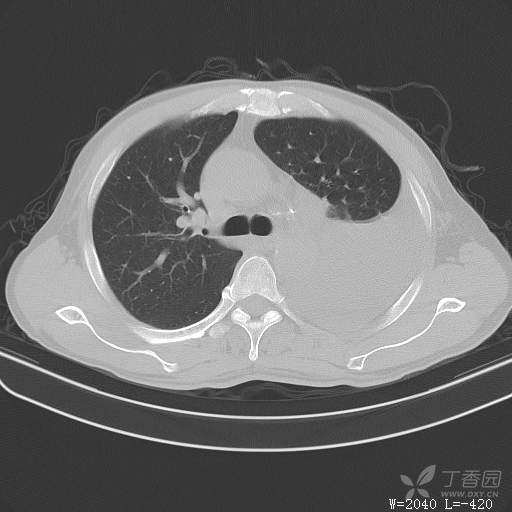

这个胸腔积液原因不寻常,大家猜猜看(得细心,这个很有意思)(俱乐部3)

简要病史:胸闷、憋气伴低热1月

体格检查:T:37.6℃;P:92次/分;R:20次/分;Bp:100/60mmHg,神清,呼吸平稳,周身未触及肿大淋巴结,右肺及左上肺叩诊清音,左下肺叩诊浊音,右肺及左上肺呼吸音粗,左下肺未闻及呼吸音,心率92次/分,律齐,无杂音。腹部平坦,软,全腹无压痛,无反跳痛及肌紧张,肝脾肋下未触及,双下肢无水肿。

临床诊断:左侧胸腔积液